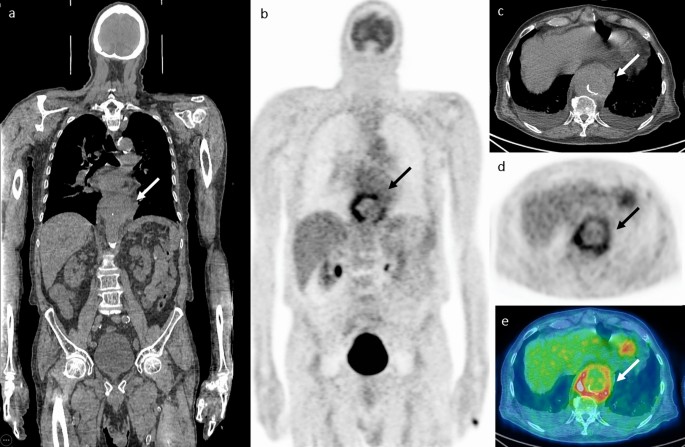

149 patients with 151 separate episodes of SAB who underwent FDG-PET/CT were included in this study. FDG-PET/CT was performed at a median of 118,13 days after the first positive blood culture. Positive findings suggestive of at least one infectious focus were observed in 107 episodes (70.8%). The most common foci were bone and joint infections observed in 58 (38.4%) of patients. Other foci involved skin/ soft tissue in 35 (23.1%), lungs in 32 (21.1%), vascular foci in 20 (13.2%), muscular foci in 16 (10.9%) and deep-seated abscesses and cardiac foci were observed in nine (5.9%) cases each6. Figure 1 shows an example of infectious focus in an aortic pseudoaneurysm.

Infectious focus in an aortic pseudoaneurysm. A 73-year-old male presented with dyspnea and was diagnosed with Staphylococcus aureus bacteremia and empyema that was drained. FDG PET/CT images (A, B coronal slices, C, D, E axial slices at the level of the lower chest) show pathological FDG uptake in a thoracic aortic pseudoaneurysm (arrows). The patient underwent endovascular aortic stent insertion and was treated with intravenous antibiotics followed by chronic suppressive oral treatment. In a follow-up visit 6 years later, the patient has no evidence of disease.